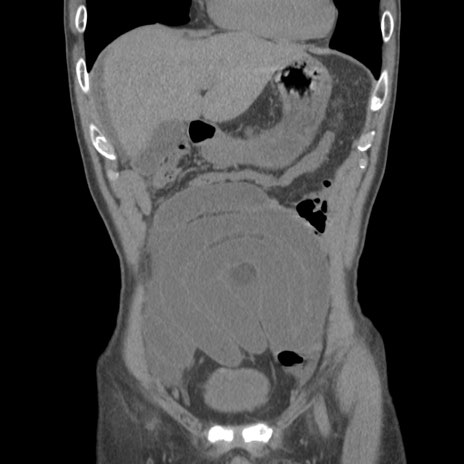

症例56 CT(冠状断像)

脂肪ウインドウ